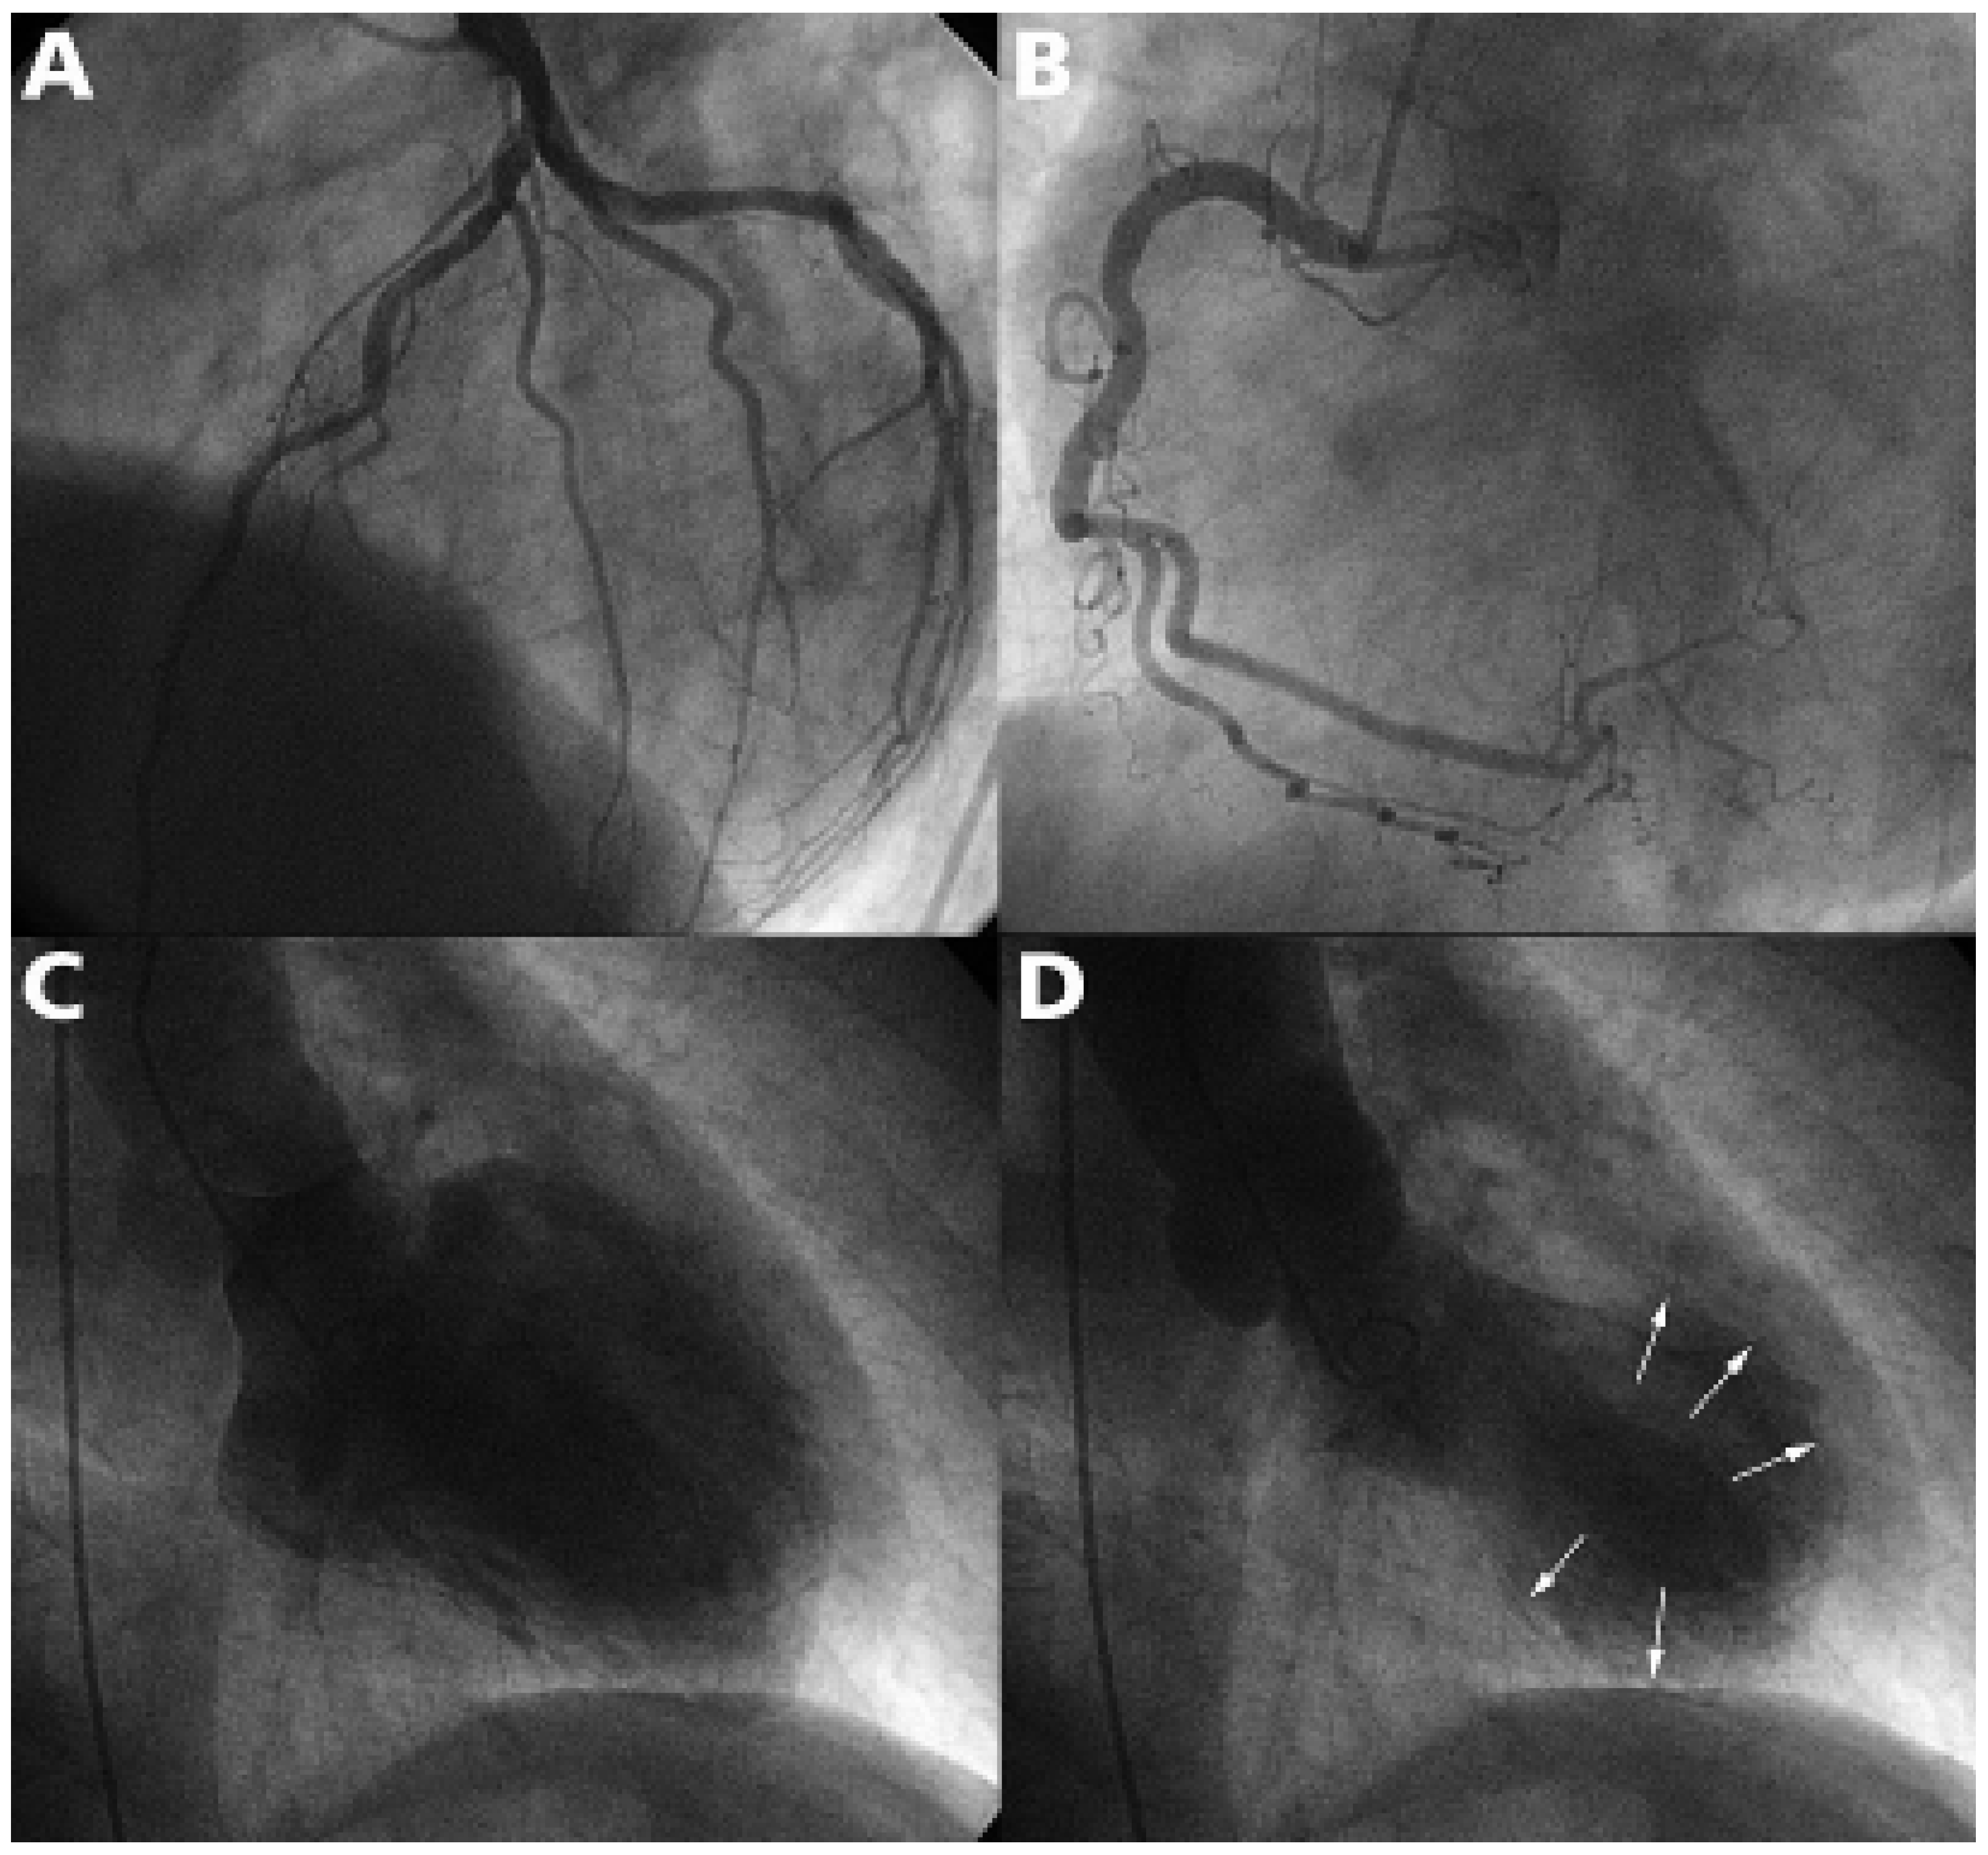

Angiographisch fanden sich offene Koronararterien mit leichten Wandunregelmässigkeiten im mittleren RIVA und der rechten Kranzarterie (Figure 2). Das Angiogramm des linken Ventrikels zeigte eine Akinesie der midventrikulären Wandregionen bei erhaltenen Kontraktionen apikal und der basalen Konstriktorebene. Angiographisch resultierte eine Ejektionsfraktion (EF) von 51%. Der linksventrikuläre enddiastolische Druck war mittelschwer erhöht (26 mm Hg).

Figure 2. Die Koronarangiographie zeigte offene Koronararterien mit diffusen leichten Wandunregelmässigkeiten der linken (A) und der rechten Kranzarterie (B). Die Lävographie zeigte eine Akinesie der midventrikulären Wandregionen (Pfeile) bei erhaltenen Kontraktionen apikal und der basalen Konstriktorebene (C: Diastole; D: Systole).